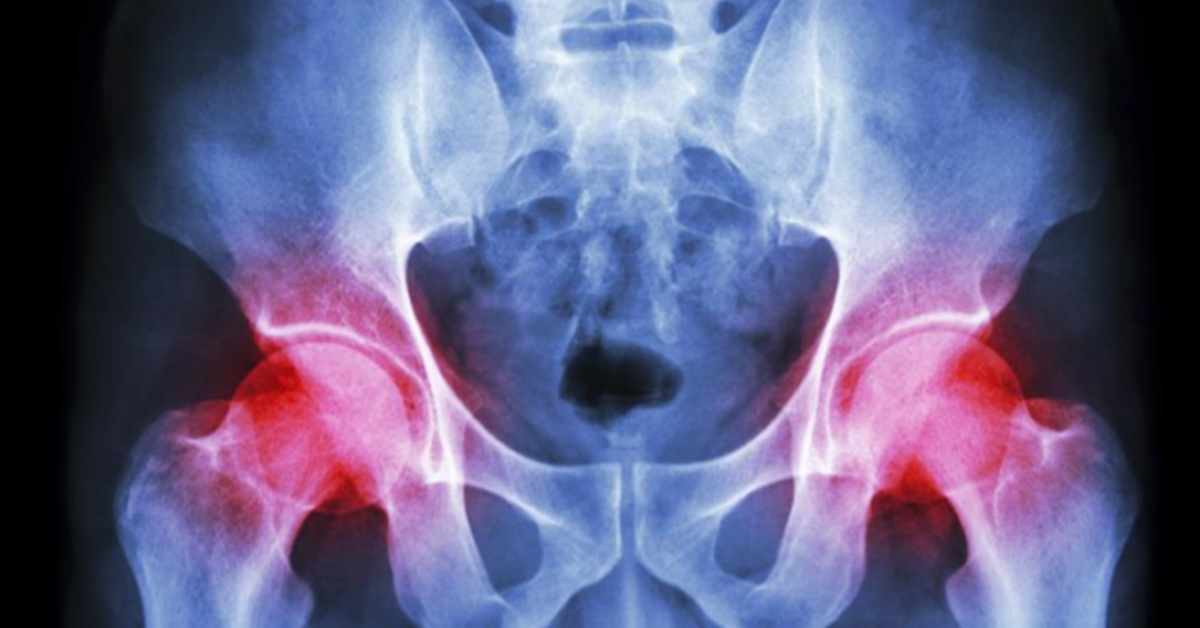

You have always enjoyed an active lifestyle until that oneday when you start to notice an unusual pain in your hip. You tried to managethe pain hoping it would get better, only to find that over time it has progressivelygotten worse. As the pain worsens you find yourself avoiding activities youonce enjoyed. After realizing that thepain will not get better on its own, you decide to see your doctor to see whatmay be going on. It’s then that you findout that the pain your experiencing is related to severe arthritis in your hipand that you need a hip replacement to resolve your pain. This can be a scary and very stressfulsituation. But it doesn’t have to be ifyou know that there are options available to help you recover faster and experience less pain after surgery.

Anterior Hip Replacement surgery means that the surgeon replaces a patient’s hip by coming from the front (anterior) of the hip. The benefit of coming from the front is that the doctor doesn’t have to cut muscles to replace the hip which makes for a significantly faster recovery compared to all the other methods of replacing a hip. All other approaches, which include posterior, lateral, and anterolateral all must cut muscles and disrupt vital tissues to replace the hip. Other benefits of anterior approach and not cutting muscles include less pain, less blood loss, less risk for dislocation, and more equal restoration of leg lengths. But the biggest thing most patients care about is the faster recovery which allows you to get back to living life without the pain and not having a prolonged recovery process. Anterior hip replacement is also so less invasive that lots of patients are candidates to have their surgery done outpatient and able to recover in the comfort of their own home with out the need for a costly hospital stay.